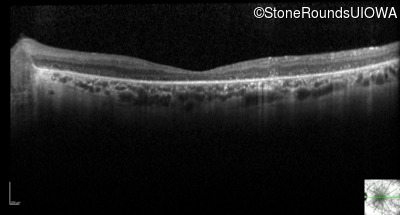

Optical Coherence Tomography - Left - 20/300 sc

Exemplar / OCT Stack

OCT Stack